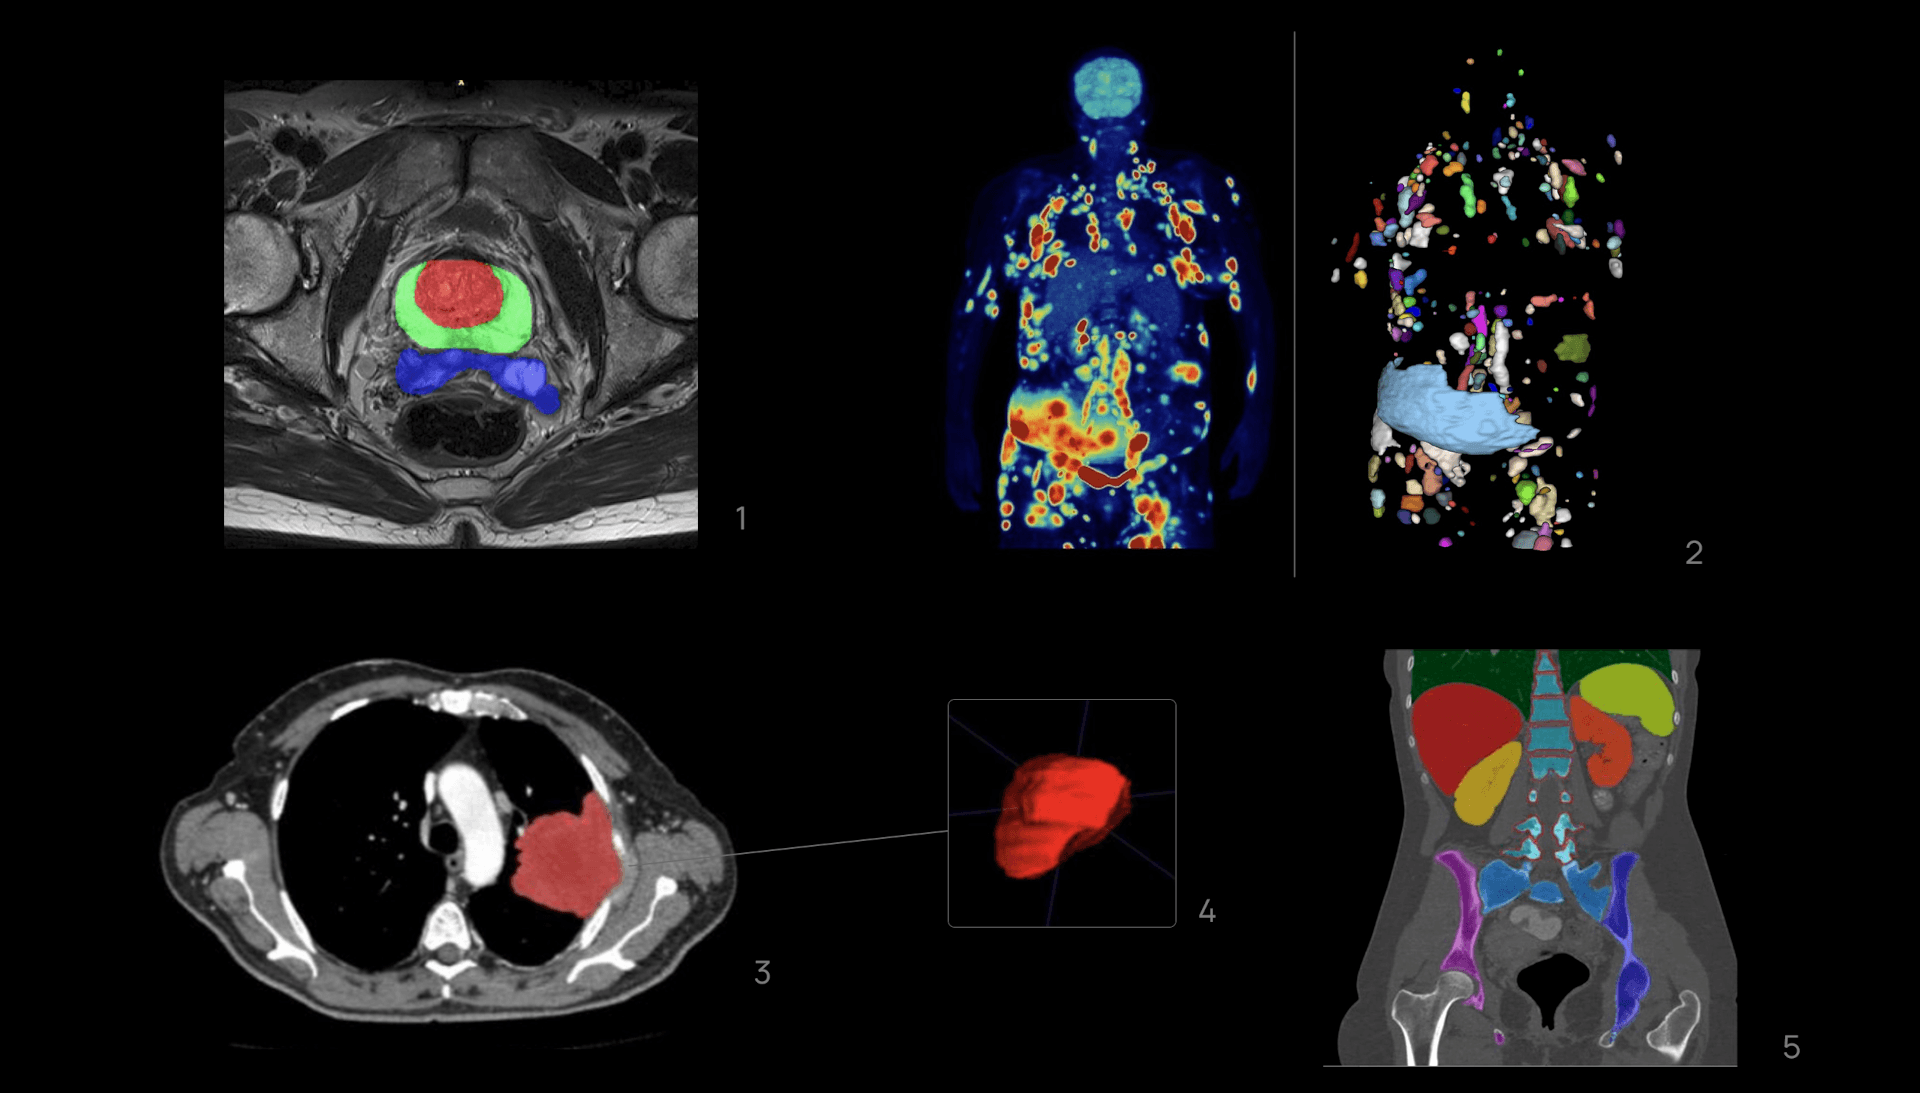

The medical AI segmentation process involves precisely identifying and delineating a region of interest (ROI) within an image. In medical image segmentation AI, these ROIs may include lesions, organs, healthy tissues, or structures, delineated in one or multiple imaging modalities, such Magnetic Resonance Imaging (MRI), Computerized Tomography (CT) or Positron Emission Tomography (PET), among others.

At Quibim, the precision in medical AI segmentation is paramount. Our accurate solutions for medical training and research provide high-quality segmentation results that serve as key elements in characterizing the aggressiveness and heterogeneity of tumors, ultimately impacting patient evolution. These segmentations are also crucial for developing AI-driven solutions capable of making predictions at both lesion and patient levels.

For this reason, a standardized segmentation process is systematically implemented in every study we manage at our company, leading to the definition of reproducible and standard protocols refined to each specific use case. Not only the segmentation of a lesion is important, but also its surrounding organs and tissues. For instance, in AI-driven solutions for overall survival (OS) prediction in lung cancer, not only is the lesion ROI considered, but also nearby structures such as lungs, heart, bone/calcium, liver, metastasis, among others.

The beauty of this segmentation lies in its voxel-by-voxel execution, providing three-dimensional insights into the ROI. This approach surpasses conventional criteria that rely on diameter measurements, thereby capturing a more comprehensive and nuanced representation of the tissue under study.

1-Segmentation of the central zone, peripheral zone of the prostate and seminal vesicles on Axial T2-wheited magnetic resonance imaging.

2-Whole body 18-FDG PET/TC imaging exam of a patient with DLBCL in the coronal plane(left) and segmentation mask where every lesion is a unique label (right).

3, 4-Segmentation of the left lung tumor mass on axial Computerized Tomography slices with 3D reconstruction.

5-Segmentation of various anatomical structures in a coronal plane on a Computerized Tomography study.